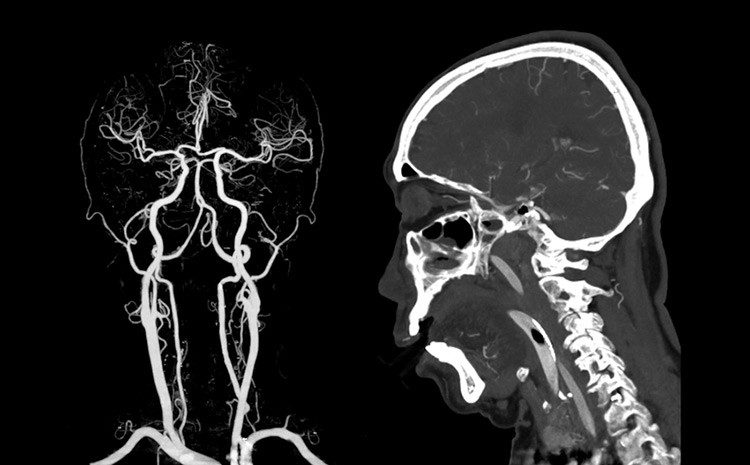

A angiografia cerebral é uma das ferramentas mais impressionantes da medicina moderna, principalmente por permitir algo que parece impossível: observar o sangue circulando dentro do cérebro em tempo real. É como colocar o órgão em “câmera lenta” e enxergar detalhes que, a olho nu, jamais seriam percebidos. Esse processo transforma informações invisíveis em imagens claras, revelando caminhos, desvios e pequenas irregularidades que podem alterar completamente um diagnóstico.

Muito além de uma simples imagem, a angiografia mostra movimento. Cada passo do contraste dentro dos vasos revela a coreografia natural da circulação cerebral. Essa sequência, quando analisada por especialistas, ajuda a entender como o sangue se comporta, onde encontra resistência e quais áreas mostram sinais de sofrimento. A técnica proporciona uma visão dinâmica, que muitas vezes define a estratégia de tratamento.

A maior beleza desse exame está justamente no detalhe. Minúsculos vasos, imperceptíveis em outros métodos, tornam-se protagonistas. Isso faz toda a diferença, porque muitas doenças graves começam nesses pequenos trajetos. A angiografia não apenas vê; ela interpreta.

Quando o contraste é injetado, a magia acontece. A partir daquele instante, os vasos cerebrais ganham destaque nas telas, e o sangue parece se mover em câmera lenta. Essa desaceleração visual é essencial porque permite observar o fluxo de forma segmentada, quase como se fosse um filme detalhado do sistema vascular. O contraste ilumina caminhos que antes estavam escondidos, revelando padrões que contam histórias sobre a saúde do cérebro.

A análise desse movimento é extremamente rica. O profissional identifica se o fluxo segue um caminho natural, se há pontos de estreitamento ou se o sangue encontra rotas alternativas. Cada detalhe importa. Um vaso que preenche mais devagar pode indicar uma alteração; um trajeto que não aparece pode sugerir um bloqueio. Nada passa despercebido.

O interessante é que, mesmo sendo um exame altamente tecnológico, a interpretação dessa “dança” exige experiência clínica. A imagem mostra, mas é o olhar treinado que entende. O contraste não apenas revela estruturas; ele traduz comportamentos, e isso torna a angiografia uma verdadeira arte dentro da medicina diagnóstica.

Com a circulação cerebral exposta em detalhes, a angiografia permite encontrar segredos que outros exames não mostram. Pequenas malformações, variações anatômicas, fragilidades de parede e irregularidades no fluxo tornam-se claramente visíveis. Essa precisão é fundamental para o planejamento de cirurgias, procedimentos minimamente invasivos e decisões clínicas urgentes.

Muitas vezes, o exame revela informações que mudam completamente a condução do caso. Um trajeto que parecia normal em outros métodos pode apresentar nuances importantes na angiografia. Essa capacidade de revelar o “não dito” é o que torna a técnica tão especial. É um exame que vê mais longe, mais fundo e mais rápido.